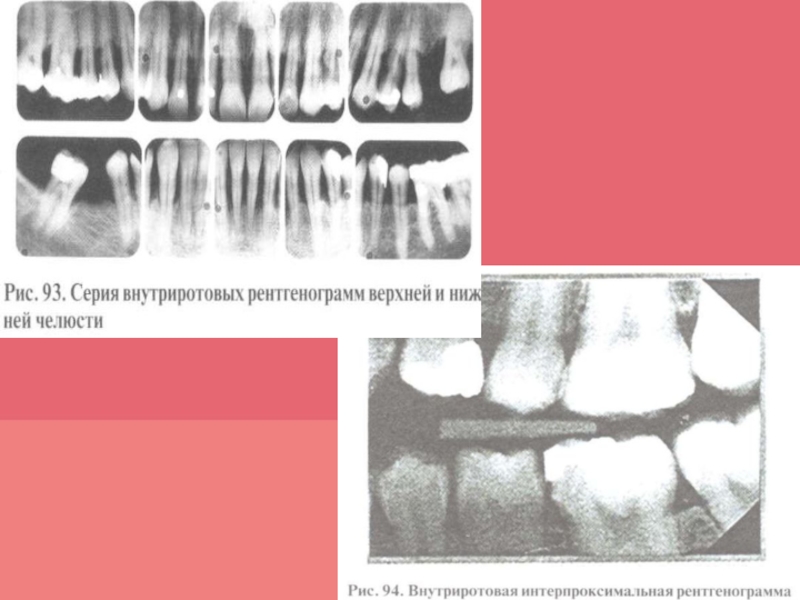

Слайд 32Рентгенологическое исследование

Рентгенологический метод позволяет определить наличие, характер, степень и

распространенность патологических изменений в костной ткани челюстей, провести дифференциальную диагностику

болезней пародонта. Для диагностики изменений пародонта оценивают внутриротовые контактные и интерпроксимальные рентгенограммы; внеротовые — панорамные рентгенограммы и ортопантомограмму, а также проводят трехмерное томографическое исследование.